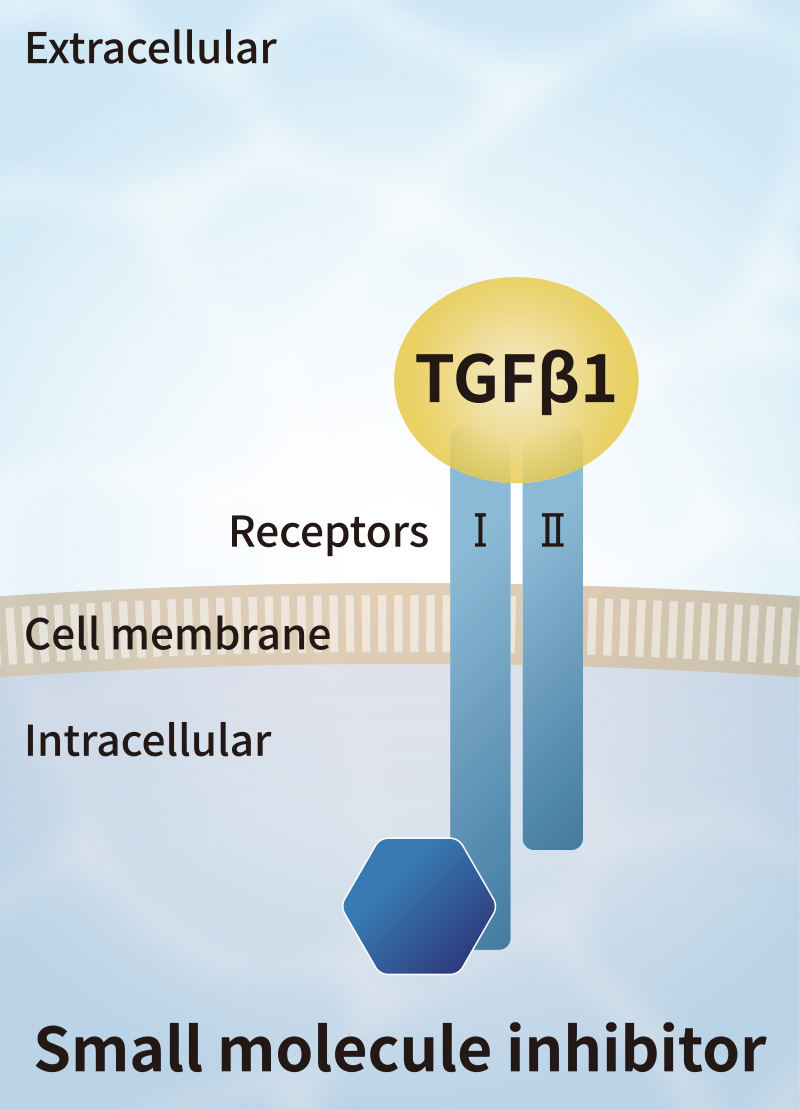

Solve challenges of conventional growth factors

Currently, FBS and recombinant growth factors are used for cell culture. However, such products have some challenges such as variation in quality among production lots, contamination by biological impurities, low stability, and extremely high prices.